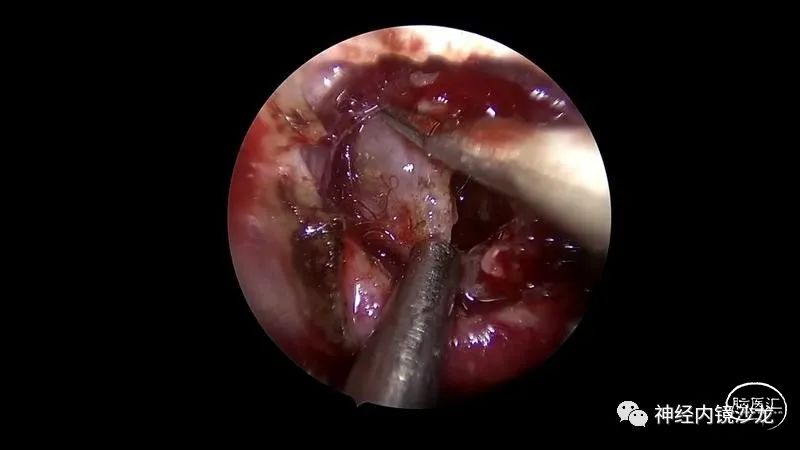

精彩图表

从事神经外科十余年,擅长神经外科肿瘤诊治,尤其是神经内镜微创手术治疗垂体瘤、颅咽管瘤、脑膜瘤等颅底肿瘤